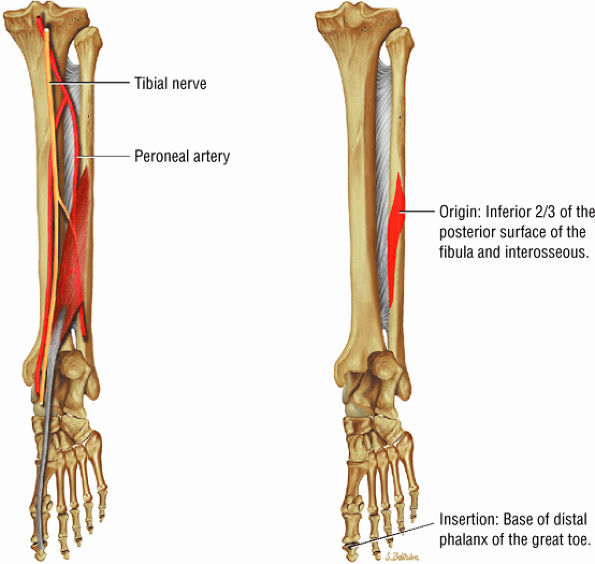

The deep group of posterior leg muscles comprises the popliteus (see discussion in Chapter 4 on the knee), the flexor hallucis longus (Fig. 5.9), the flexor digitorum longus (Fig. 5.10), and the tibialis posterior (Fig. 5.11).

FIGURE 5.9 ● FLEXOR HALLUCIS LONGUS The flexor hallucis longus (FHL) flexes the great toe and plantarflexes the foot. The FHL is susceptible to injury during extremes of ankle plantarflexion and metatarsophalangeal dorsiflexion. The proximal sheath, 10 to 12 cm in length, has no mesotenon and may communicate with both the ankle joint and the sheaths of the flexor digitorum longus and tibialis posterior.

FIGURE 5.10 ● FLEXOR DIGITORUM LONGUS The flexor digitorum longus (FDL) flexes the phalanges of the lateral four toes and plantarflexes the foot. The FDL is superficial to the flexor hallucis in the sole of the foot. Paratenonitis of the FDL is more infrequent than involvement of the flexor hallucis longus.